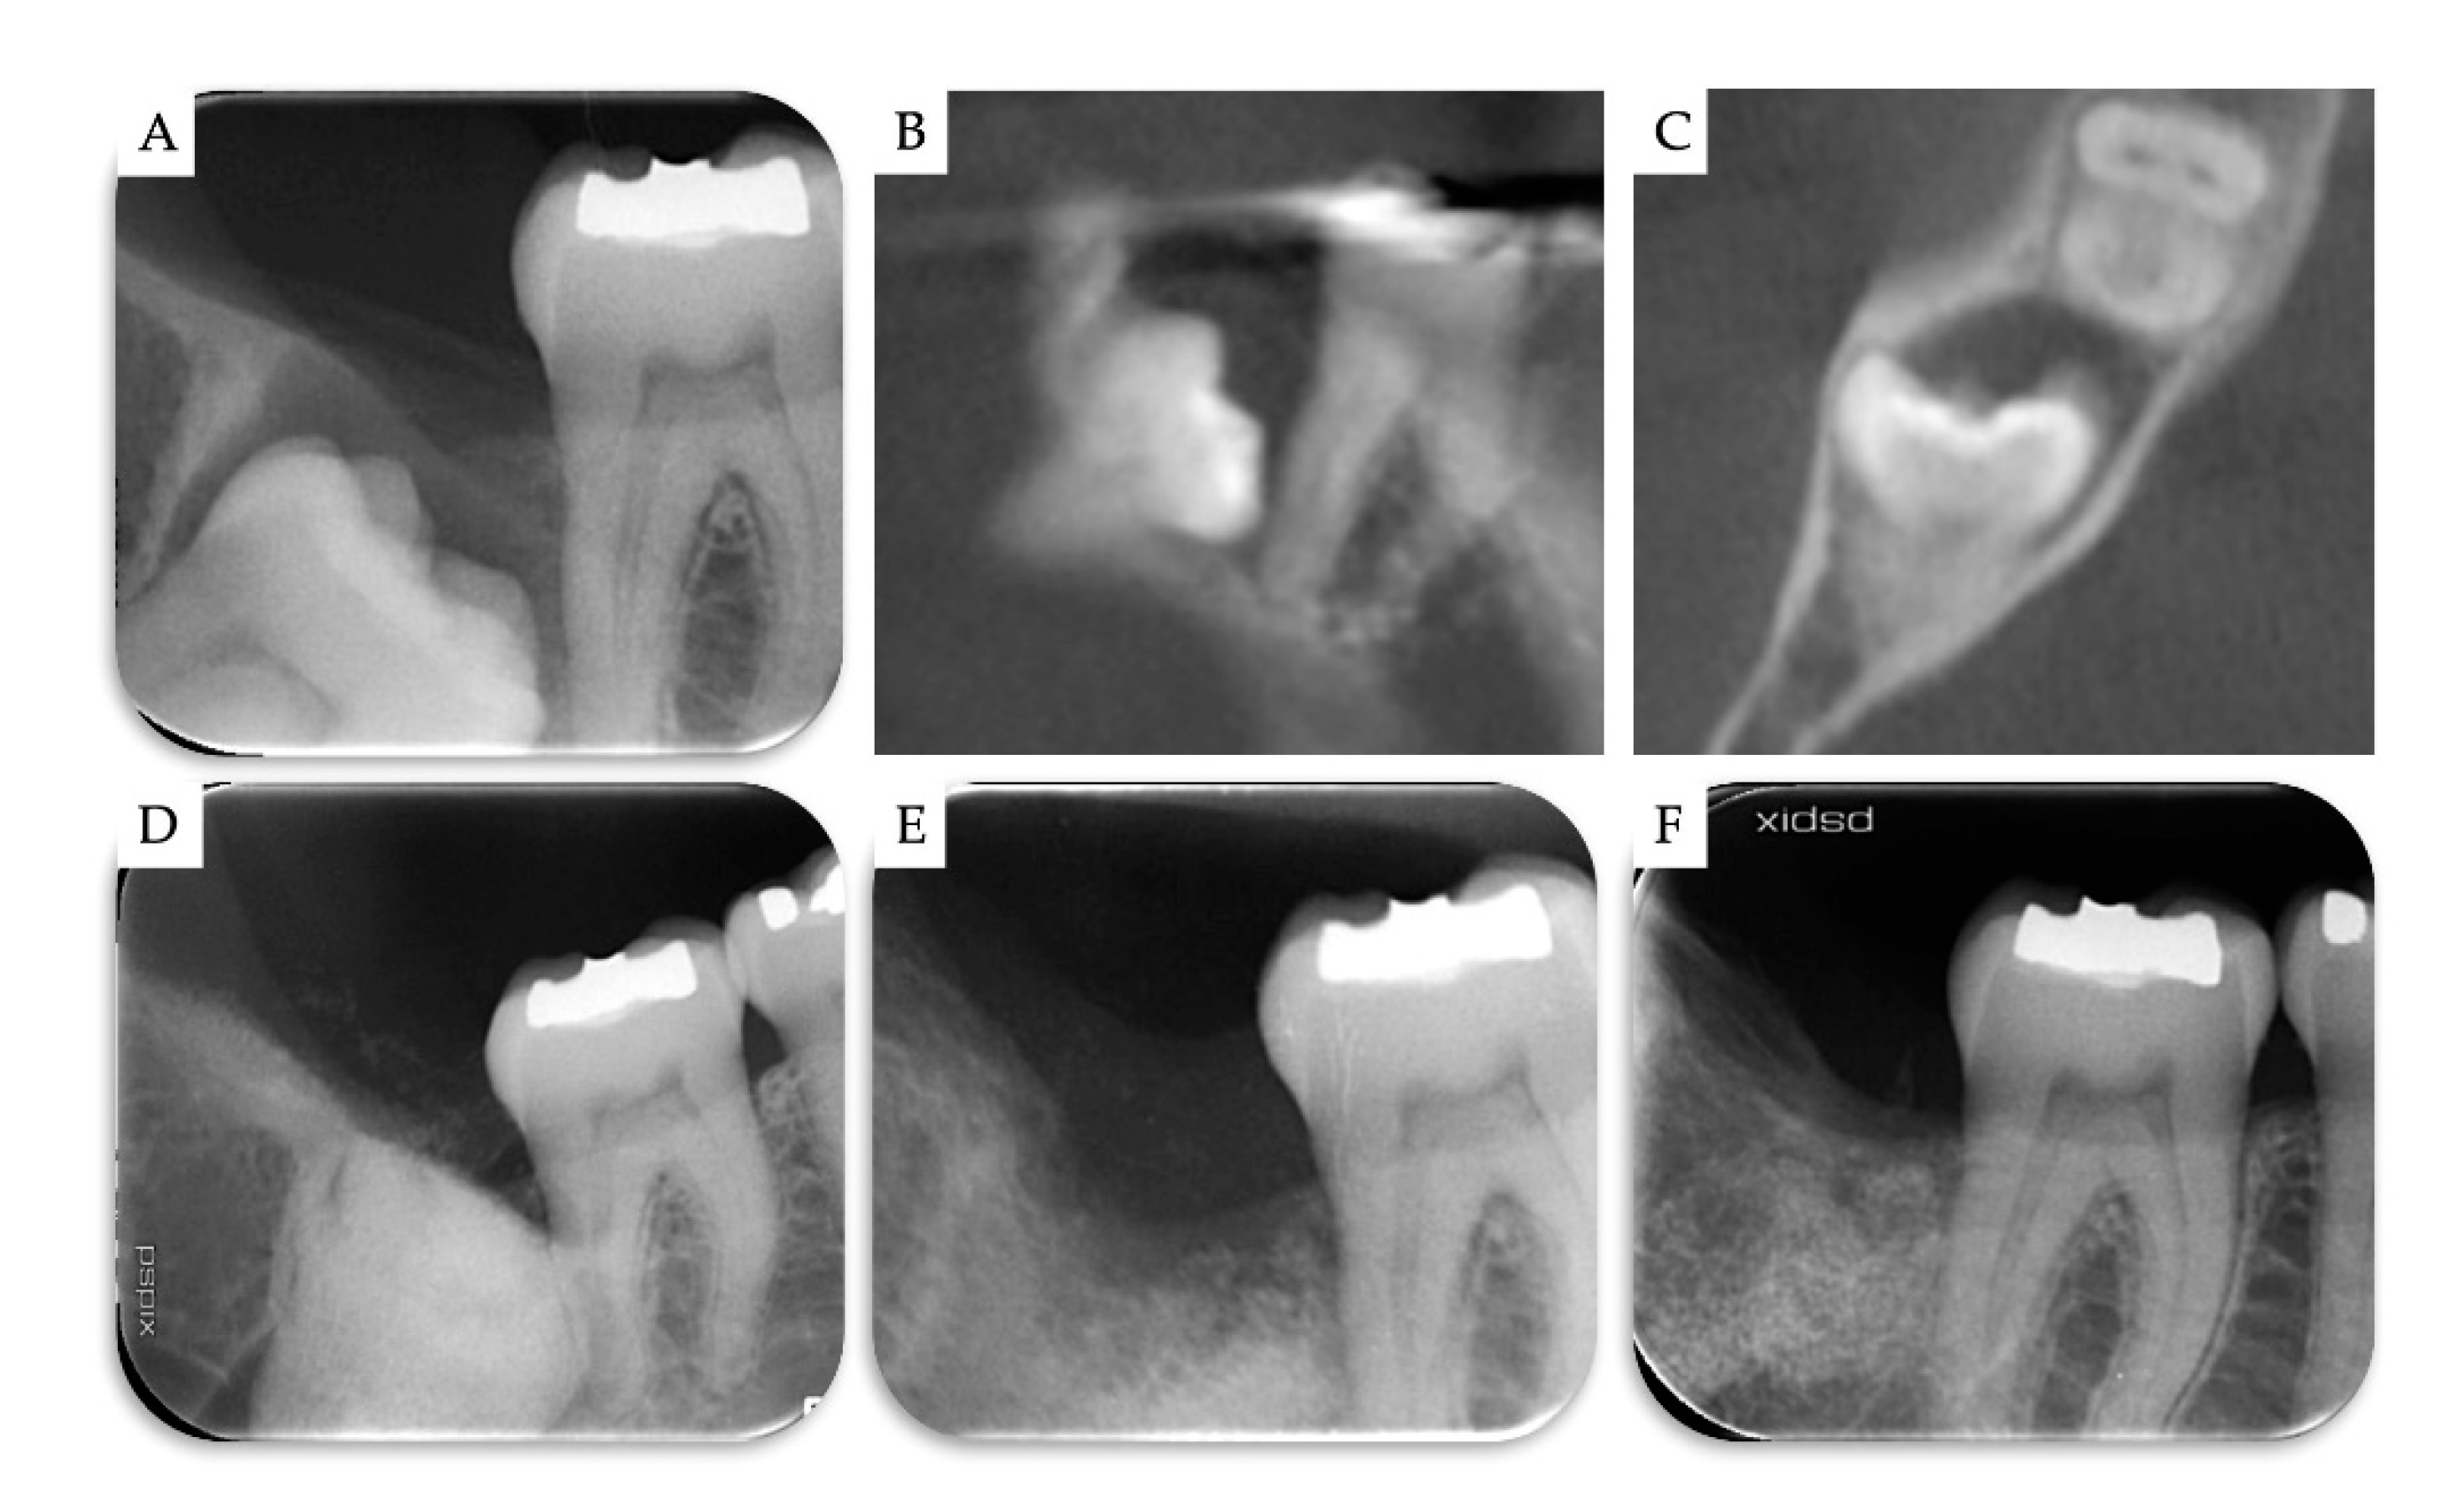

| Case | Gender | Age | Smoker | M3 | Impaction | Follow-Up (years) | PD T0 (mm) | PD T1 (mm) | BD T0 (mm) | BD T1 (mm) | BG (mm) |

|---|---|---|---|---|---|---|---|---|---|---|---|

| 1 | F | 51 | No | 48 | Mesio-angular | 2 | 12 | 3 | 11.1 | 5.2 | 5.86 |

| 2 | F | 36 | No | 38 | Horizontal | 2 | - | 1 | 7.4 | 1.3 | 6.1 |

| 3 | M | 42 | No | 38 | Horizontal | 1 | - | 2 | 10.2 | 4.4 | 5.79 |

| 4 | M | 34 | No | 48 | Horizontal | 1 | - | 2 | 8.6 | 2.1 | 6.51 |

| Mean | 40.75 | 1.5 | 2.00 | 9.33 | 3.25 | 6.07 | |||||

| SD | 6.61 | 0.5 | 0.71 | 1.43 | 1.6 | 0.28 |